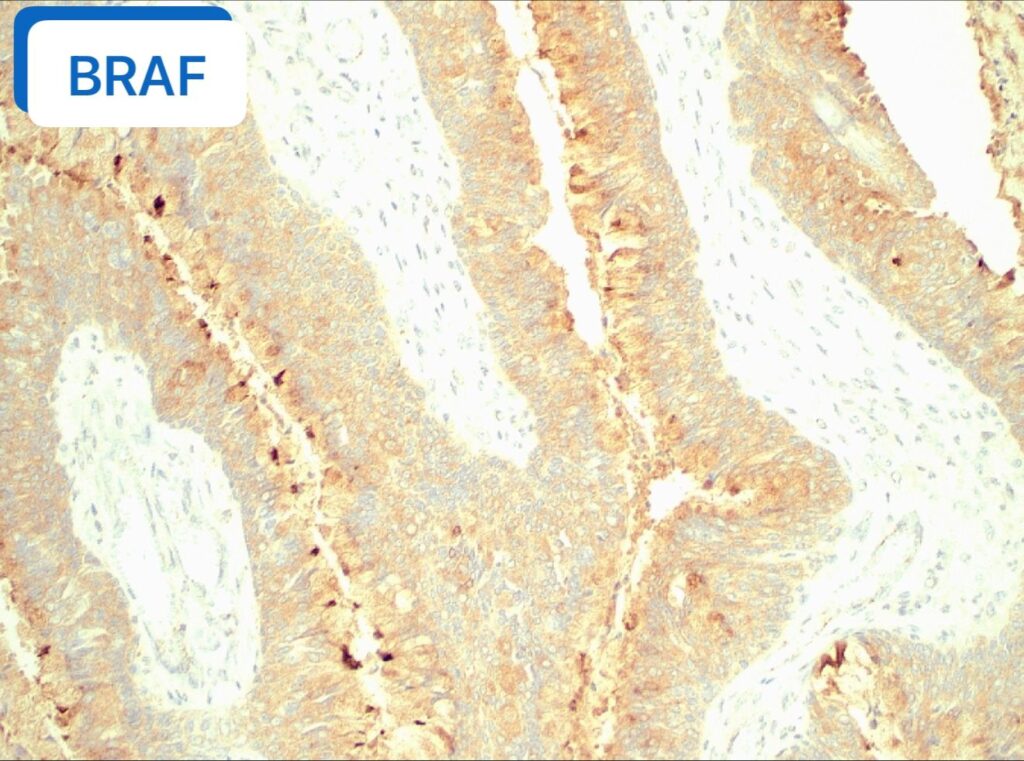

🔬 【免疫组化(IHC)一锤定音】

- BRAF V600E: 阳性(图4) 最终诊断:纤毛黏液结节性乳头状肿瘤(CMPT),无浸润性癌证据。